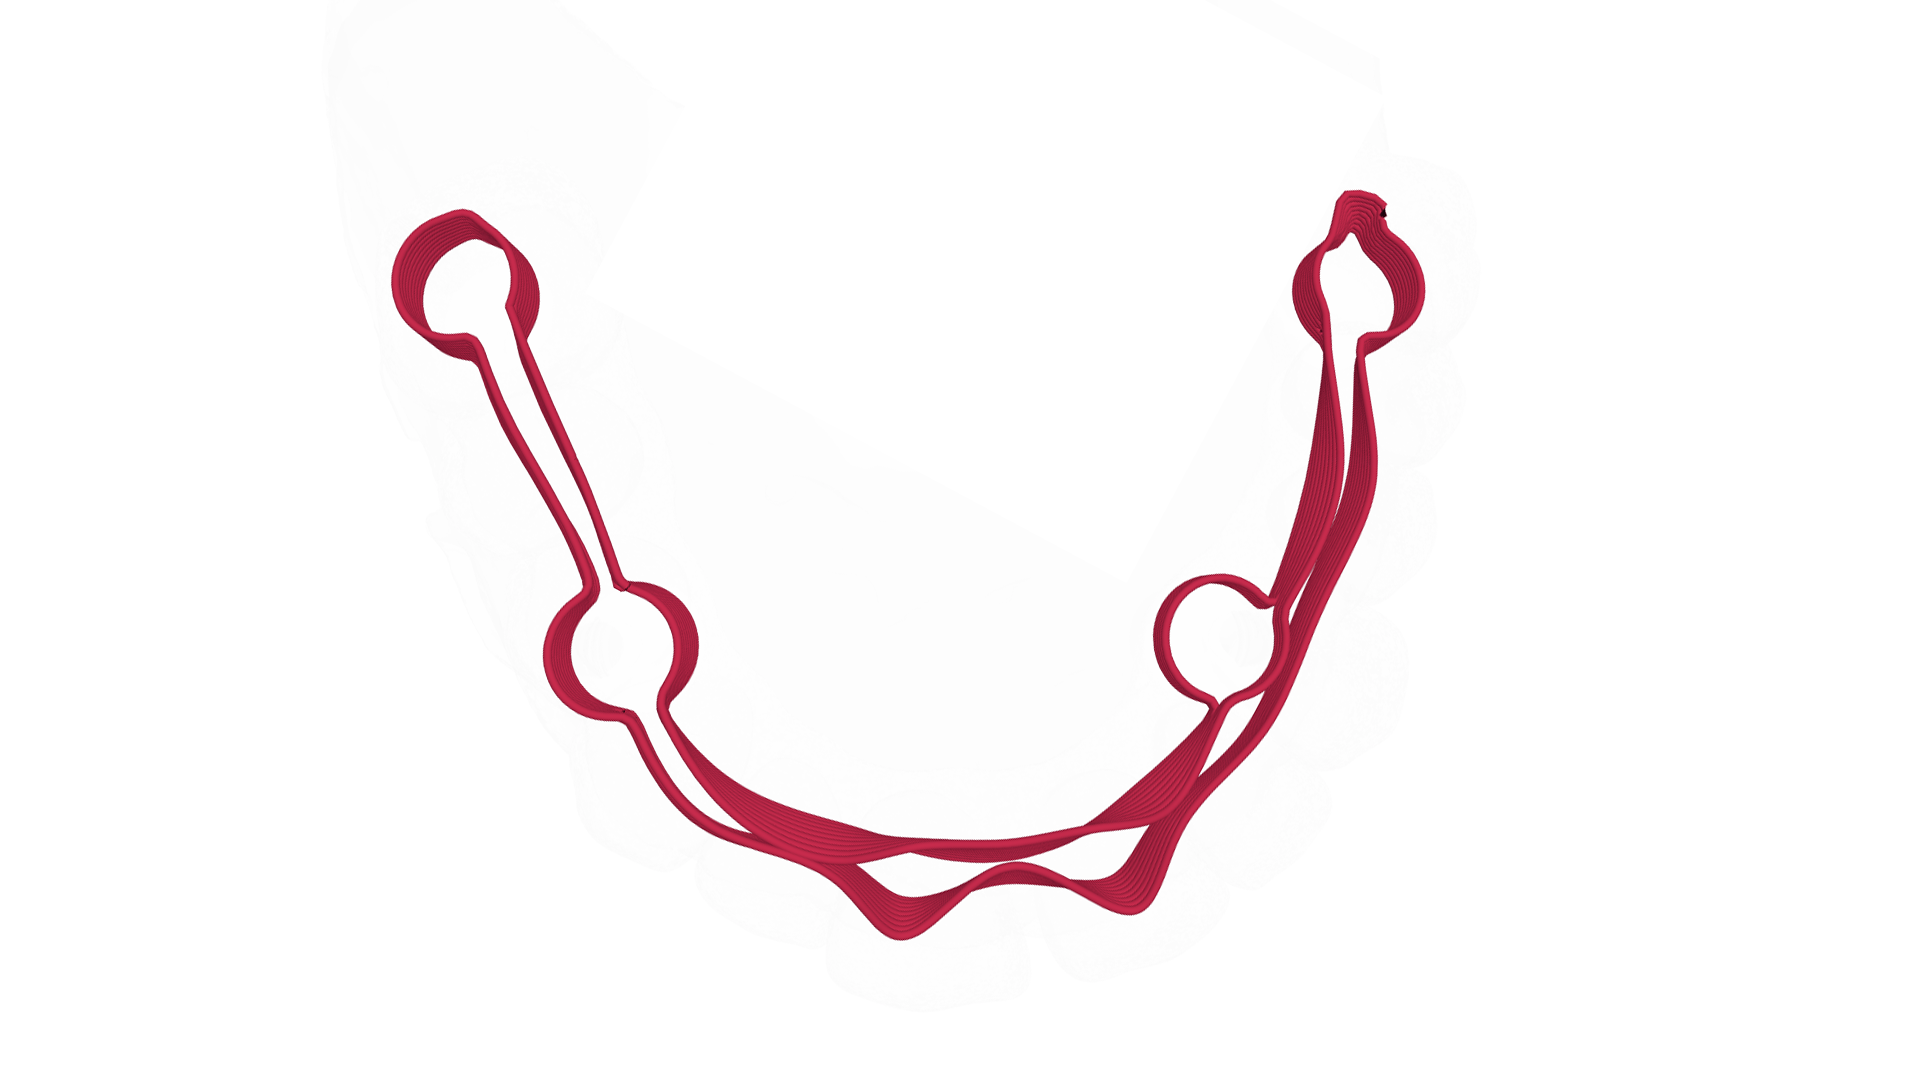

Fig. 15 Barra di rinforzo progettata dal software di Hi-Fiber

Fig. 16 Visualizzazione digitale della barra Hi-Fiber

Fig. 17 Visualizzazione digitale laterale della barra Hi-Fiber